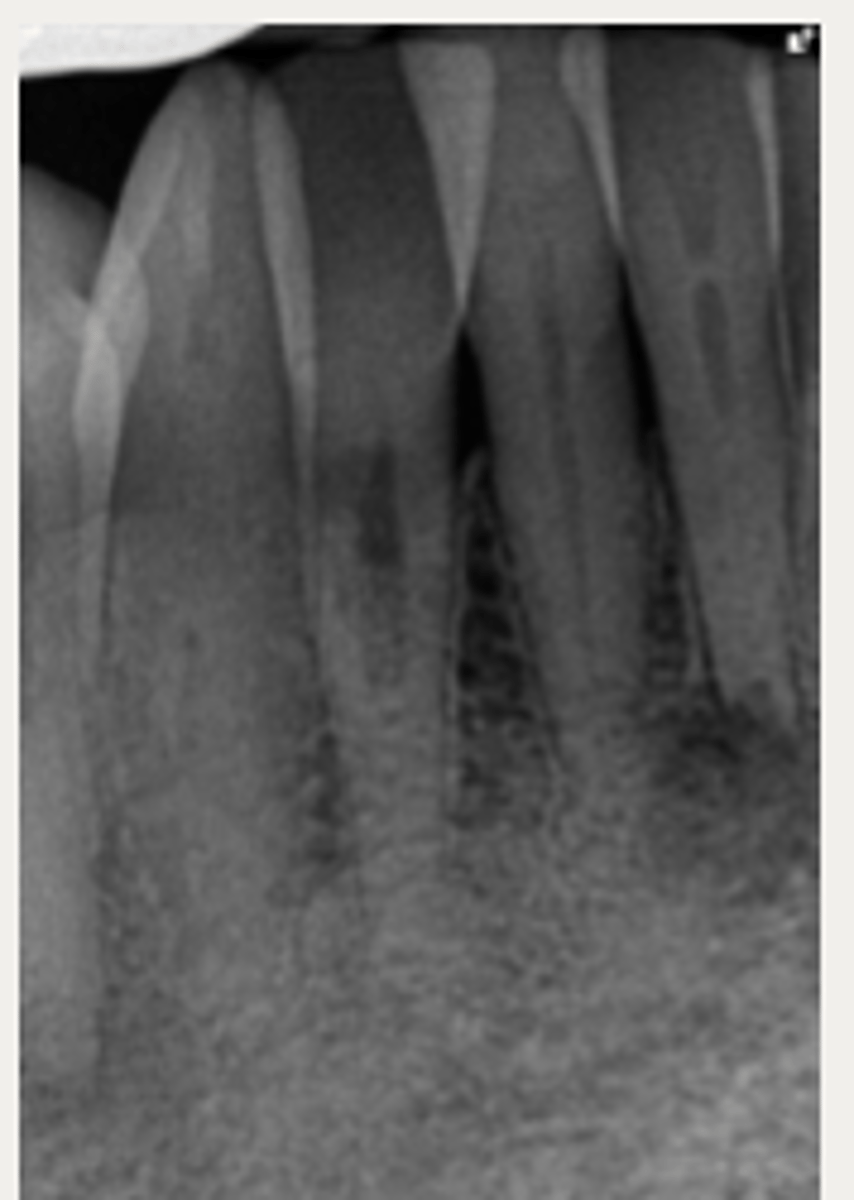

External cervical resorption (Invasive Cervical Resorption)

ID the type of resorption:

- Usually an incidental radiographic finding, especially for less advanced lesions

- Variable appearances; may be a well-defined or irregular radiolucency around the cervical aspect of the tooth

- A portal of entry is always present in the cervical region of the tooth

- The chamber/canal outline is often visible as the innermost layer of predentin around the chamber is not resorbed

Patient presents with these radiographic findings, what type of resorption?

- Incidental finding

- Radiolucency around cervical aspect of tooth

- Portal of entry present in cervical region

- Chamber/canal outline is visible

What type of lesion is similar to internal resorption but is distinguished by taking an off-angle PA in which the lesion moves?

Internal inflammatory resorption

If you take an off-angle PA and the lesion does NOT move, what do you suspect?